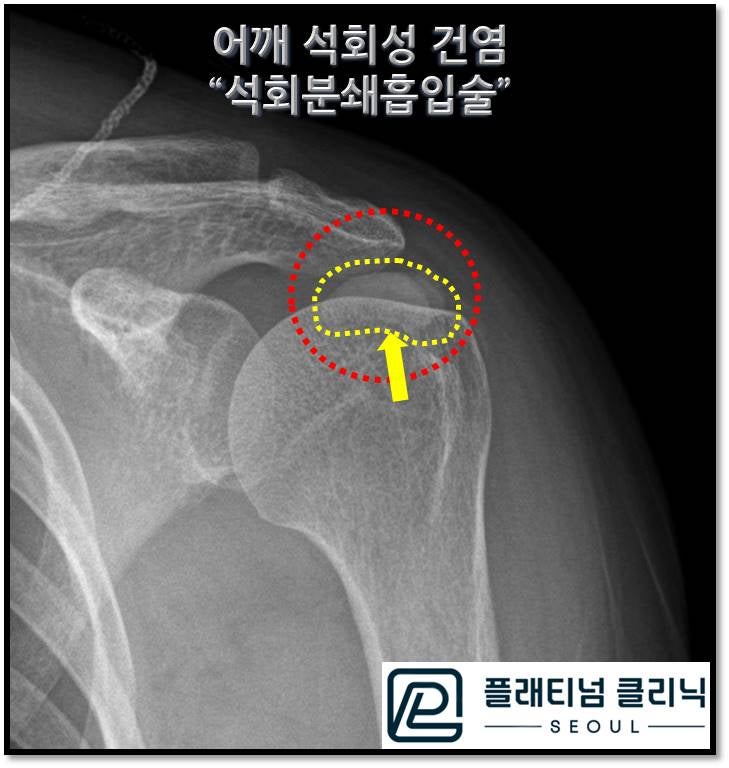

X-ray 를 보면 노란 점선으로 표시된 엄청난 양의 석회가 관찰됩니다.